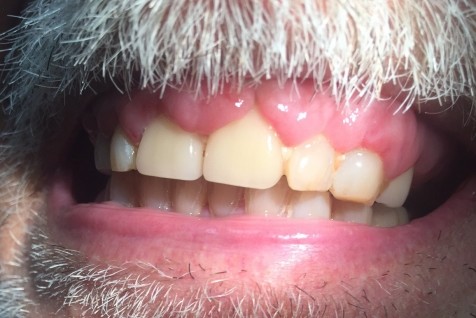

Gingival hyperplasia is an enlargement or overgrowth of the gum tissue, also known as the gingiva, around the necks of the teeth. It is an increase in the size of the gingival tissues and thus the term overgrowth is many times used in place of the term hyperplasia.

Gingival overgrowth can be caused by several mechanisms but will have very similar appearances. A study in the journal Histopathology describes the condition as "a small papillary or velvety bright red gingival overgrowth that bleeds easily." However, the overgrowth can be extensive and round in appearance. It is usually found on the front of the teeth and can be on the tongue side in some cases.

One of the causes is inflammation. The inflammation can be induced by poor oral hygiene or from a dental appliance like orthodontic braces. Other factors include systemic conditions (like hormonal imbalances or leukemia), medications or heredity conditions, according to the American Academy of Oral Medicine (AAOM). Also, localized overgrowth can be a benign or malignant lesion.